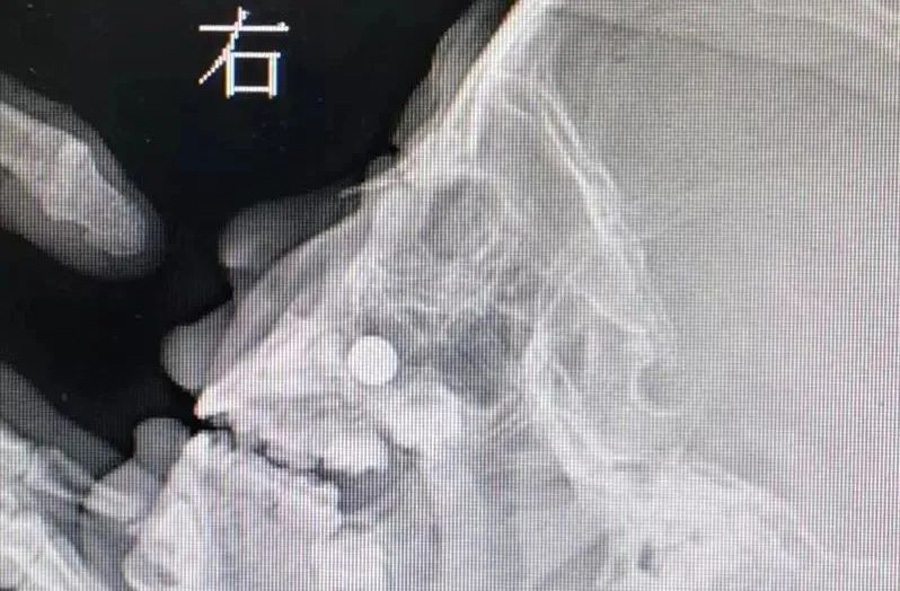

3月23日,120急救车将1名患儿送至a片网站 。患儿3岁,来时明显看出鼻子不舒服。妈妈说,前一天儿子把纽扣电池塞右侧鼻子里了,但在当地医院没取出来。如果真的是纽扣电池,那就危险了,因为电池产生的腐蚀性物质及微电流会造成鼻腔黏膜腐蚀伤,甚至后期可能出现鼻中隔穿孔。门诊医生接诊后,未能看到鼻道中有明显异物,耳鼻喉科开放急危重症绿色通道。由于患儿及家长核酸结果未回报,耳鼻喉科医生在三级防护下做了鼻咽镜检查。在患儿下鼻道底部,发现有黏膜肿胀以及典型的纽扣电池异物放电导致的“冒泡”现象,但异物被肿胀的黏膜包裹,大小及形态显示不清。鼻咽部平片同样显示鼻腔底部有圆形金属异物。

由于异物位置特殊,以及患儿不配合,门诊不能顺利取出异物,急诊全麻取出是最好的办法。在全麻下,耳鼻喉科副主任李莉萍经过20多分钟定位、钩取,才将异物取出来。取出的纽扣电池颜色发黑,患儿右侧鼻腔黏膜也已被腐蚀成了黑褐色。经过给药处置、鼻腔消炎等治疗,第三天患儿出院回家了,后期需定期复查。